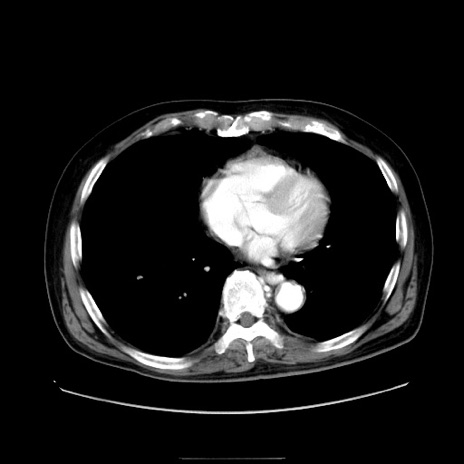

症例30(横断像)

【症例】80歳代男性

【主訴】臍周囲痛

【現病歴】約6時間前から臍下部痛が出現。次第に腹部膨隆・背部痛も生じてきたため来院。背部痛の場所は変化しない。

【身体所見】意識清明、BT 36.3℃、BP  131/87mmHg、P 87bpm、SpO2 100%(RA)、臍周囲自発痛・圧痛あり、反跳痛なし、自発痛部位に一致して板状硬あり、腹部膨隆、腸雑音減弱、CVA tenderness両側陰性。

【データ】WBC 19600、CRP 0.33